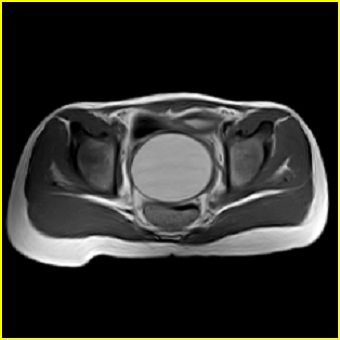

女、15岁、下腹疼痛2天,排尿困难1天。查体:处女膜闭锁,距处女膜约4至5cm处扪及一约5cm直径的圆形包块,张力较高,触痛明显、欠活动。b超提示子宫增大伴宫内增强回声团。

影像意见:子宫直肠陷凹积血。

更正影像意见:阴道积血。

处女膜闭锁,阴道积血,子宫积血.

子宫及阴道积血。

处女膜闭锁,伴子宫及阴道积血.